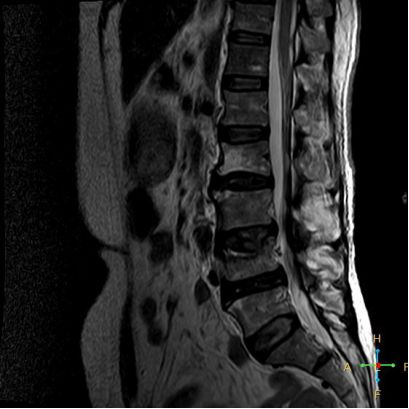

3 恶性压缩性骨折 椎体上下径变窄而前后径增大,椎体后部皮质后突,后角一般表现圆钝,无上翘,常呈球形突出,致椎管狭窄,即膨胀性盘状破坏,硬膜囊和脊髓受压。

——恶性压缩性骨折MR信号特点—— 由于肿瘤组织的侵犯,T1WI上椎体呈弥漫性低信号,T2WI呈高信号,增强扫描呈明显不均匀强化。

转移瘤 椎弓根改变:椎弓根膨大仅见于恶性压缩性骨折,故为其特异性,可作为鉴别诊断的依据。

椎旁软组织肿块:在转移瘤中,受累椎体周围多出现分叶状或肿瘤样软组织肿块,此征象仅见于恶性压缩性骨折。故,椎旁薄环状软组织与瘤样软组织肿块是鉴别骨折性质较有特征性的征象。